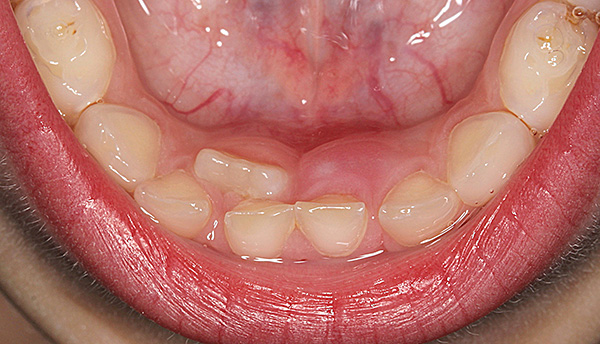

Abaixo na foto, você pode ver como é um conjunto completo de dentes decíduos na mandíbula inferior:

Normalmente, os ossos da mandíbula da criança têm uma forma semicircular, os dentes estão espaçados e estão em contato íntimo, a dentição superior se sobrepõe à inferior. As superfícies posteriores dos molares temporários estão localizadas no mesmo plano, uma em relação à outra.